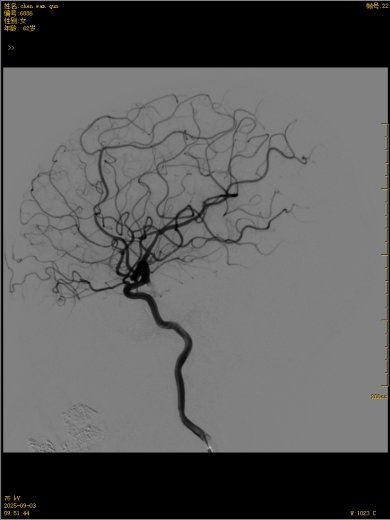

这款国产创新技术的优势不止于疗效:通体显影设计让支架定位精准到毫米级;超弹性材质与优化编织工艺实现极致贴壁,兼顾支撑力与柔顺性,适配复杂迂曲脑血管;操作更轻巧、创伤更小,仅需大腿根部米粒大小切口即可完成手术,可实现患者术后可快速康复。本次手术中,团队在DSA引导下精准释放支架,全程耗时短、出血少,术后造影显示,动脉瘤内血流即刻变得迟缓,载瘤动脉通畅,重要分支血管保护完好。患者术后恢复良好,未出现任何神经功能障碍,术后不久即快速康复出院,重获健康,恢复正常生活工作。